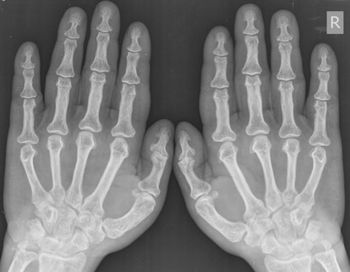

A 7-year-old male presented with pain after falling on an outstretched hand.